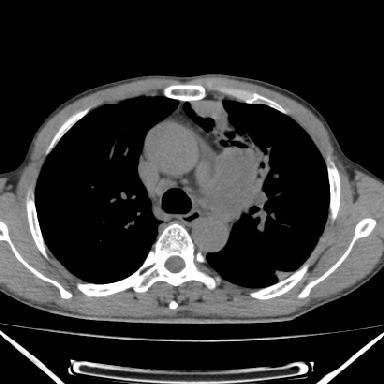

以下是引用zjzjr在2007-3-23 17:24:00的发言:[br]双侧肺门淋巴结明显肿大,以左侧为著,支气管受压变窄,肺内可见结节状及絮状高密度影,边缘模糊.考虑淋巴瘤肺内浸润.